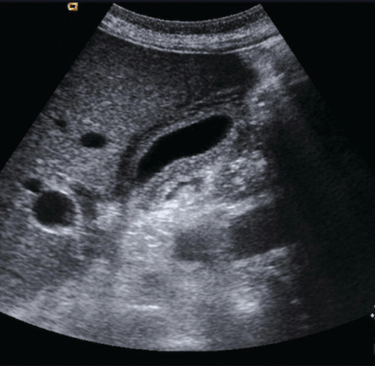

Our abdominal course unfolds as a systematic, high-yield survey of visceral imaging, Doppler interpretation, and clinical reasoning.

Early sessions focus on image ergonomics and machine optimization, giving learners tactile confidence and geometric orientation to three-dimensional anatomy across the abdomen. From there, we move through a comprehensive organ-by-organ protocol, teaching learners to interpret anatomy, echogenicity, Doppler blood flow, and physiologic relationships with clarity.

Hands-on practice is continuous. Learners repeatedly apply Doppler to vascular structures, correlate findings with pathology, and learn how to document each organ and vascular bed in a methodical way.